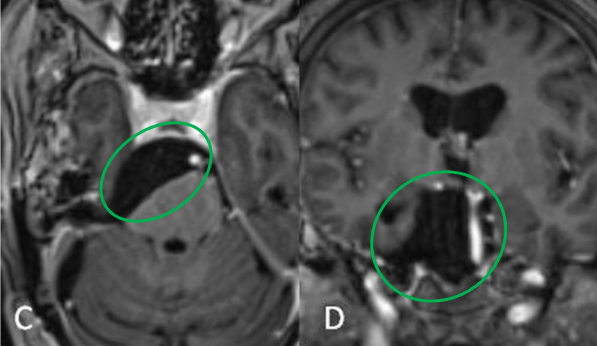

术后:C术后轴位及D冠状位T2加权磁共振成像(MRI)显示,肿瘤已实现大体切除,同时观察到神经血管结构得到有效减压。

最终脑部核磁检查揭开了真相:一个巨大的岩斜区脑膜瘤正潜伏在她大脑深部——有重要的血管、颅神经,肿瘤巨大已经严重压迫脑干,广泛累及幕上,导致了梗阻性脑积水,必须手术切除。每一秒的延误,都可能造成不可逆的神经损伤。

经过周密的术前准备,福教授手术团队为患者进行了颅内肿瘤切除术。微型联合岩骨入路(mini-CTPA),成功实现了肿瘤的近全切除,无神经功能缺损。